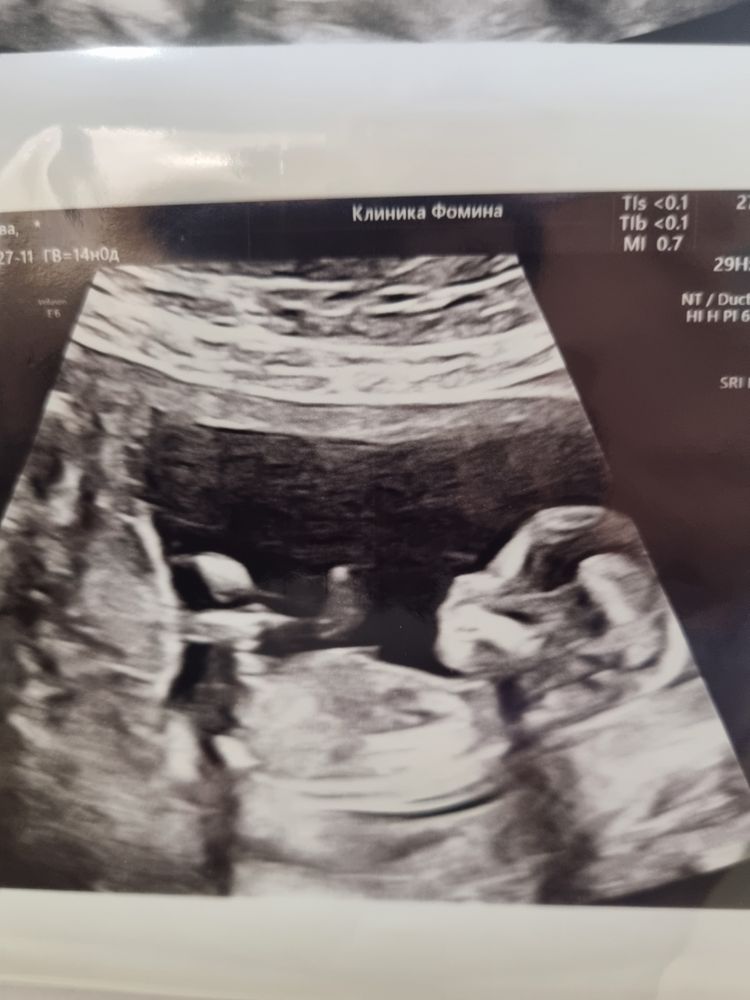

Какой красивый мужчина растёт☺️ Пусть там все у него хорошо будет ✨

🤍 расти пацанчик